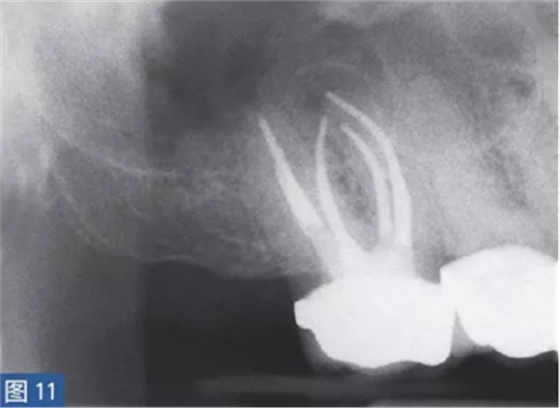

慢性根尖周膿腫(圖10 和11)是由長期持續(xù)的炎癥引起的。膿液穿通骨和口腔黏膜,并通過口腔黏膜或上皮的瘺管流出。這些通到表皮的瘺管通??赡茏鳛槠つw損傷而被錯(cuò)誤處置。此外,瘺管也可能存在于牙周并通過齦溝引流。瘺管可以部分或完全地被上皮所包繞,這些上皮又被炎性結(jié)締組織包圍。

臨床診斷顯示牙髓電活力測(cè)試結(jié)果為陰性。除非瘺管閉合,否則叩診和觸診通常都不會(huì)引起疼痛。放射學(xué)檢查,根尖周組織表現(xiàn)從無變化到發(fā)生明顯變化。

圖10:17 牙齒CAA。術(shù)前放射學(xué)檢查,利用牙膠尖顯示瘺管?;颊咭?7 牙齒局部瘺管而前來就診,訴無特殊臨床癥狀。

圖11: 17 牙齒CAA。根管治療12 個(gè)月后。